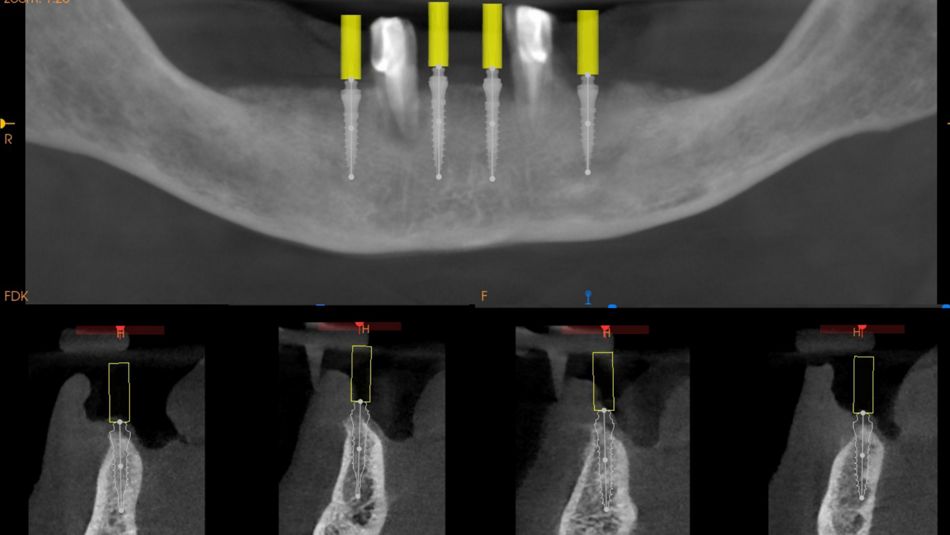

1a. 1b. Pre-operative panoramic X-ray and CBCT showing moderate generalised bone resorption in the mandible, a reduction in vertical dimension in the posterior region and the planned positioning of mini- implants.

1a

1b